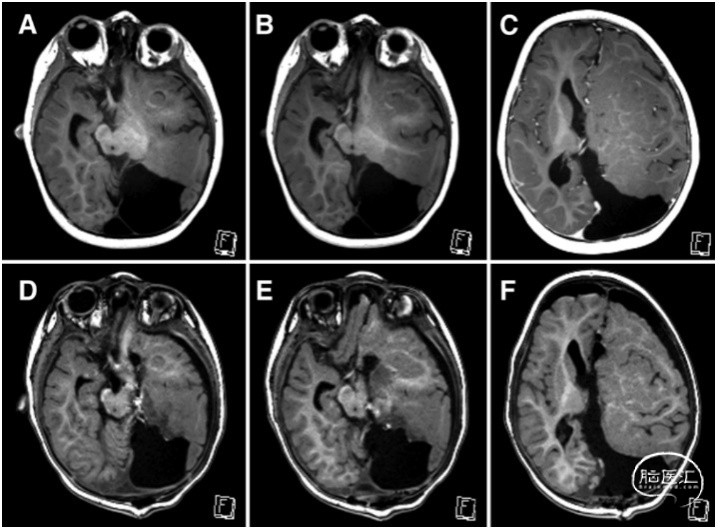

图2. MRI-T1加权轴位成像;A-C为术前,D-F为术后显示解剖切开。A和B.左侧视路、前脑和额叶之间的关系。D和E.在左侧视路上方可见丘脑与中脑切开、半球间隙切开。C.大脑纵裂静脉是胼胝体前部切开的标志。F.显示胼胝体切开。术中患儿取俯卧位,安装Mayfield头架固定,采取神经电生理监测和导航辅助。作左枕部正中线旁5.5cm头皮直切口,小骨瓣开颅。C形剪开硬膜,翻向矢状窦侧。可见左侧枕部重度发育不良(图3)。